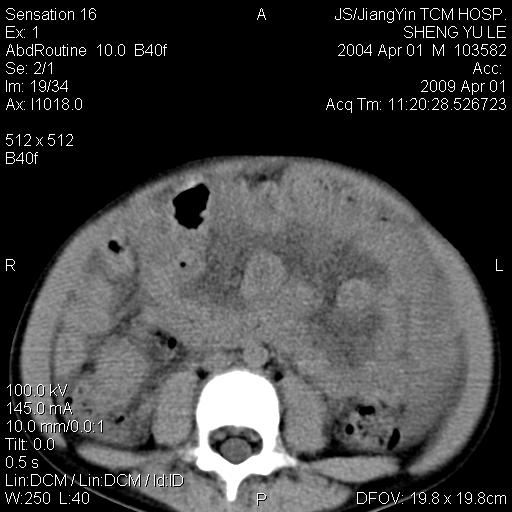

m,5岁。尿痛尿频数天。既往无病史。ct平扫腹盆腔积液。膀胱壁明显增厚。另可见心包增厚。wbc5万,骨髓穿等结果。请指教。

膀胱影像表现结合临床应该是急性膀胱炎症,但为什么有腹水呢?双肾输尿管无扩张,泌尿系压力应该不大不至于引起尿外渗,应该是腹膜感染引起的,但楼主没有提及相关症状,腹膜及膀胱结核?患者白细胞5万(结核不至于这么高啊),脾脏增大,是不是有白血病?进一步检查。。

腹水,膀胱壁增厚,wbc5万,结合临床,支持感染性疾病---感染性腹膜炎、腹水,急性膀胱炎,败血症。期待结果。